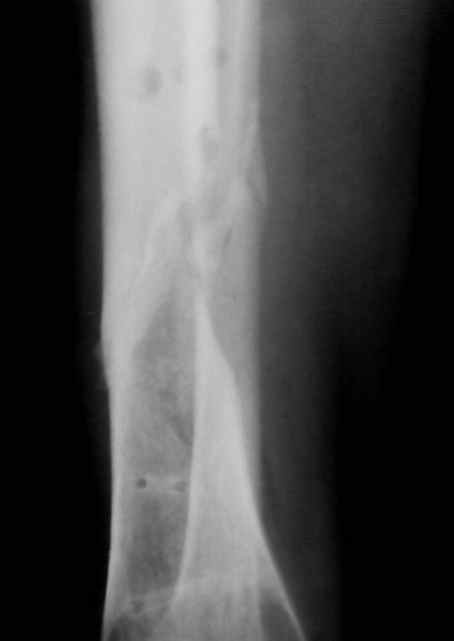

Больная 54 года, 5 м. назад открытый оскольчатый перелом 2-3 тип, Первично ЧКДО, открытое ведение раны, при этапных некрэктомия " ушел" осколок внутренней стенки б/бецовой кости, 7 сутки пластика м/тканями ,вторичные швы.

Контакт отломков только по спирали наружной стенки,заживление раны полное, на 3-4 месяце ЧКДО воздействие на регенерацию микродистрациями , 5 месяц снят аппарат по причине нестабильности и реакции м/тканей. В данный момент проблем с тканями нет, на Р-граммах псевдоартроз, клинически подвижность,больная ходит в ортезе с дозированной нагрузкой.Местно рубцовый процесс 3х5 в зоне перелома.

Вы имеете дело не с псевдоартрозом, а с замедленно срастающимся переломом.

Прежде,чем обсуждать план лечения, я рекомендую проанализировать причины замедления сращения.

Возможно они связаны с тяжестью травмы, нестабильностью аппарата с самого начала,инфекционным процессом или заболеванием больного, снижающим потенциал сращения.

Будьте добры послать снимки до операции . а также после операции, на которых видна компановка аппарата Илизарова. Кстати на представвленных рентгенограммах в аппарате есть спица с напайкой, проведённая проксимально перелома через обе кости... Если можно, объясните необходимость такого проведения.

Кроме того в плане обследования обязательно надо исключить наличие вялотекущей инфекции - Анализы крови и скенировние костей Технеций + Галий или меченные лейкоциты.